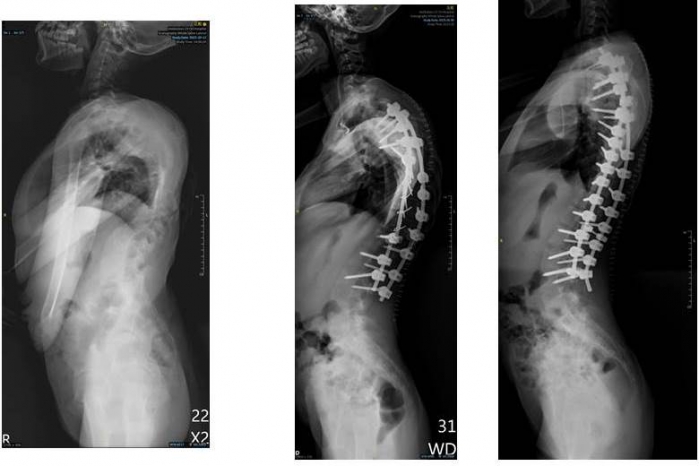

回台後他與院方討論,立刻獲得院方的全力支持,除了與嘉基脊椎微創中心主任黃儀鴻醫師合作,另外也請到台北慈濟的骨科權威曾效祖醫師參與手術。考量到誠心的神經與血管長年受壓迫,不適合一次變動太多以免造成癱瘓風險,因此分別於今年10月20日、11月3日各進行一次手術,兩次手術時間合計超過30個小時,成功讓側彎角度來到57度,從外觀上來看,誠心的背部已打直,心肺也不再受壓迫,身高更從135公分「長高」到150公分,接下來她還需要長期的復健,訓練呼吸與恢復重心。

嘉基院長姚維仁表示,醫院的「人道與海外關懷基金」善款由社會大眾捐獻,多用在海外義診以及弱勢者的國際醫療需求。在台灣由於有健保,醫療可近性也高,大部分的脊椎側彎患者會能及時就醫,先透過背架或其他方式矯正治療;但若持續惡化到了40度,便會歸類為重度脊椎側彎,建議進行手術。誠心小妹妹因為受限於經濟因素、當地醫療與政治現況,無奈之下才使側彎發展到驚人的160度。現在台灣已鮮少有如此嚴重的脊椎側彎個案,這次手術是由多位有經驗的醫師共同執刀,並憑藉嘉基智慧手術大樓最先進高端設備,以最新的脊椎固定骨釘以及高階術中影像系統、術中導航、神經監測等,帶著各界的支持一起讓誠心的生命成功轉彎,也祝福她有幸福健康的未來。